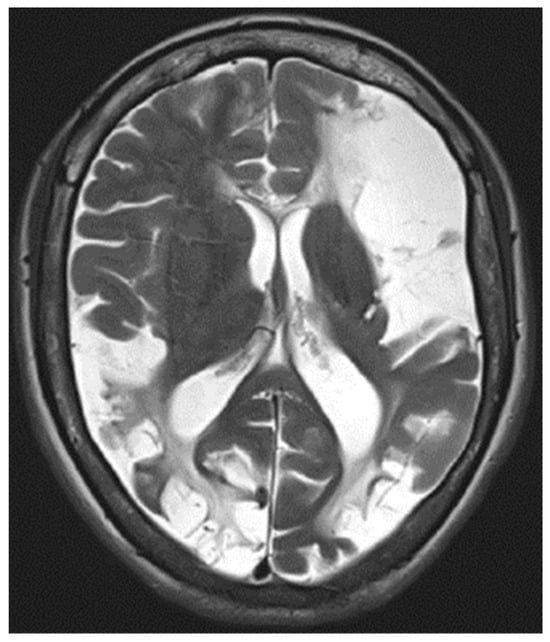

An MRI of the head (Figure 3) showed multiple long-standing ischemic lesions in all regions of the cerebral vasculature and significantly reduced blood flow in all arteries of the anterior circulation (Figure 4). Doppler ultrasonography of the extracranial vessels did not show any abnormalities. EEG revealed marked interhemispheric asymmetry—diffusely slowed, not well-organized brain activity in the right hemisphere, and in the left, not well-organized alpha rhythm with frequent single or multiple temporoparietal spikes. Abdominal ultrasound, consultation with a vascular surgeon, duplex ultrasonography of the lower limb vessels, consultation with a cardiologist, ECG, and echocardiography were all unremarkable for any pathology. Computed perimetry for the evaluation of visual field defects could not be accomplished due to excessive myopia, reduced visual acuity (20/800), and cognitive impairment. The serum level of valproate was 61.68 μg/mL.

Figure 3. T2-weighted MRI image showing diffuse ischemic lesion throughout the cerebral hemispheres.